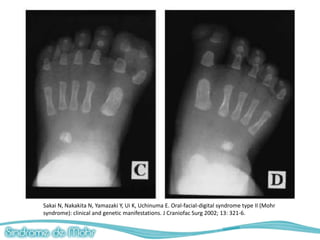

Alteraciones digitales

• Polidactilia postaxial/preaxial en manos y pies

(Hexadactilia)

• Sindactilia

• Braquidactilia

• Polosindactilia de los dedos gordos del pie.

– Radiografias (manos, pies, cabeza)

Naohiko Sakai, et al. Oral-Facial-Digital Syndrome Type II (Mohr Syndrome): Clinical and genetic manifestations

Sakai N, Nakakita N, Yamazaki Y, Ui K, Uchinuma E. Oral-facial-digital syndrome type II (Mohr syndrome): clinical

and genetic manifestations. J Craniofac Surg 2002; 13: 321-6.